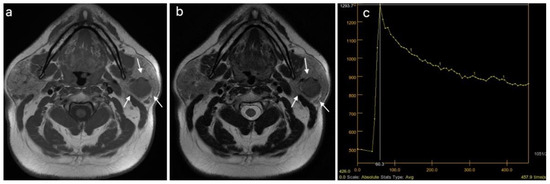

| MRI, T1 weighted image, n (%) | 0.024 | ||

| Hyperintense signal | 1 (5.26) | 7 (24.14) | |

| Mixt signal intensity | 3 (15.79) | 11 (37.93) | |

| Hypointense signal | 15 (78.95) | 11 (37.93) | |

| MRI, T2 weighted image, n (%) | <0.001 | ||

| Hyperintense signal | 12 (63.16) | 3 (10.34) | |

| Mixed signal intensity | 6 (31.58) | 20 (68.97) | |

| Hypointense signal | 1 (5.26) | 6 (20.69) | |

| DCE MRI, TIC curve, n (%) | <0.001 | ||

| Type A | 14 (73.68) | 0 (0) | |

| Type A, C | 1 (5.26) | 0 (0) | |

| Type B | 3 (15.79) | 11 (37.93) | |

| Type C | 1 (5.26) | 18 (62.07) | |

| DCE MRI, TTP (ms), median (IQR) | 210 (166.15–228.9) | 88.5 (82–101.9) | <0.001 |

| DWI MRI, ADC × 10−3 mm2/s, median (IQR) | 1.5 (1.25–2.1) | 0.86 (0.73–1) | <0.001 |